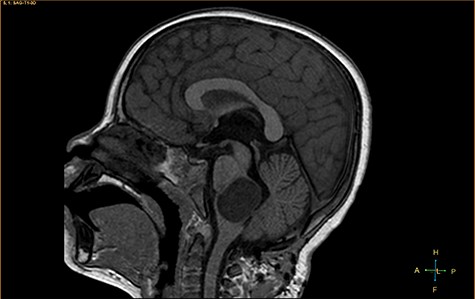

A 3-year-old male, who suffered from a sudden, tonic–clonic seizure, followed by a short period of unconsciousness, was instantly transported to Children’s Hospital 2. The patient’s medical history was normal. No neurological deficits were detected during the clinical assessment, and laboratory tests and electroencephalography were within acceptable ranges. The clinician performed a brain magnetic resonance imaging (MRI) scan, with contrast agent. No lesions were recognized in the supratentorial structures. A clear boundary cystic mass (27 × 25 × 26 mm3) was located in the medulla oblongata, without perilesional vasogenic edema. Hydrocephalus was not observed. The signal intensity of the mass was low on the sagittal T1-weighted image (Fig. 1) and high on the axial T2-weighted image (Fig. 2). On coronal fluid-attenuated inversion recovery imaging, the mass was isointense relative to the parenchyma, but the intensity was higher than that of cerebrospinal fluid (CSF, Fig. 3). On susceptibility-weighted imaging, no indicators of hemorrhage or ossification were observed within the mass. The mass was partially hyperintense on diffusion-weighted imaging (DWI) and slightly hypointense on the apparent diffusion coefficient (ADC) map. The mean ADC values of the parenchyma, mass and CSF were 0.71, 1.3 and 1.59 × 10−3 mm2/s, respectively (Fig. 4). On T1-weighted imaging, with contrast enhancement, the thin wall of the mass was very slightly enhanced, and we observed a tiny nodule inside the mass that was strongly enhanced (Fig. 5). With a provisional diagnosis of pilocytic astrocytoma, the patient underwent surgery to completely eradicate the tumor. Eventually, the histopathological result revealed a typical EC (Fig. 6). The postoperative period was uneventful, and the patient was discharged after 2 weeks.

Axial T2-weighted image, showing a hyperintense, cystic mass inside the medulla oblongata. Exceptionally, the lesion appears to progress from extra-axial to intraparenchymal (arrow).

Two widely accepted hypotheses have been suggested to explain the establishment of extra-axial and intra-axial ECs. Theoretically, ECs form due to aberrations in ectodermal residues or the sequestration of ectodermal components during an early stage of gestational growth, between the 3rd and 5th weeks. The remnants of these ectodermal cells eventually proliferate, forming an EC [3, 4]. Retrospectively, the findings shown in Fig. 2 appear to show the progression of the lesions from the extra-axial to the intraparenchymal medulla oblongata; therefore, we have contributed additional evidence to reinforce the hypothesis regarding the primitively extra-axial root of EC development.